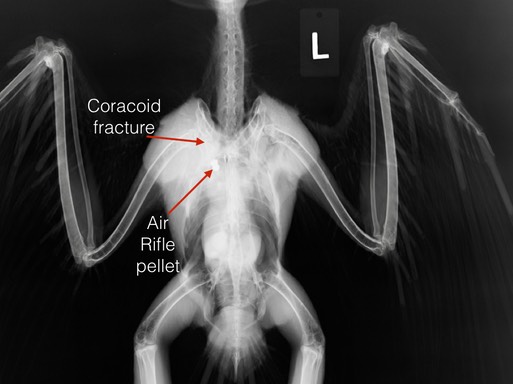

Swainson’s Hawk 18-266

The saddest case admitted this past week was a female Swainson’s Hawk who had been shot. The physical exam revealed she had a brood patch, indicating she was either incubating eggs, or young chicks (likely considering the time of year).

Coracoid fractures have about a 15% chance of healing well enough for the bird to be released whether the fracture is repaired surgically or the wing is immobilized with a bandage. We have chosen the latter method. It will be at least a month, and perhaps two, before we know if we will be successful. In the mean time, the young will very likely die.